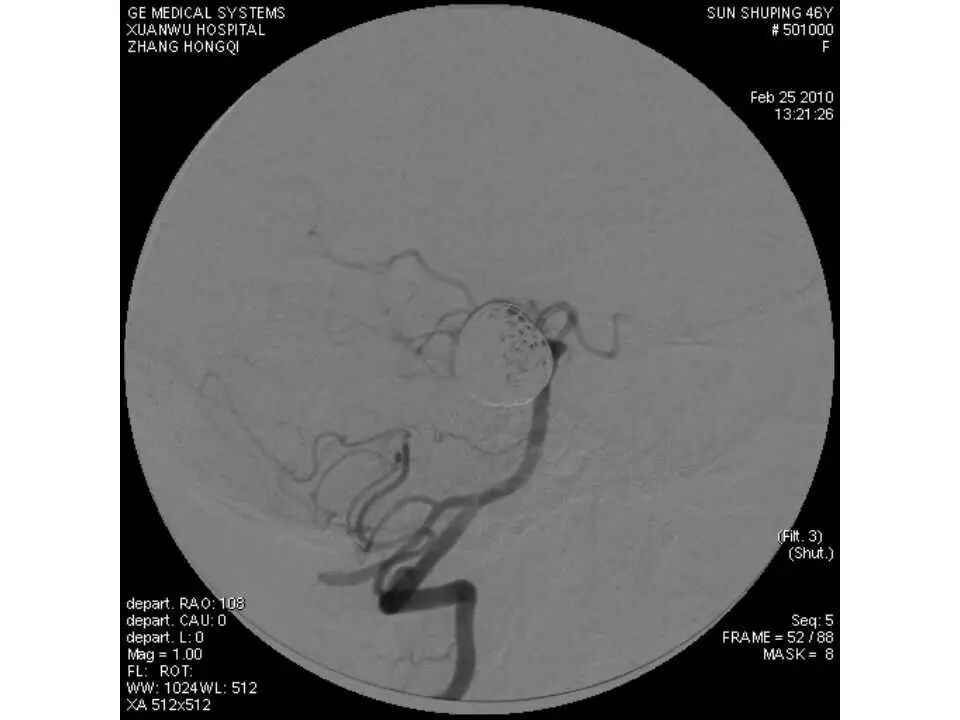

今天为大家分享的是“强生医疗CNV-神经介入专栏”第十五期,由首都医科大学宣武医院何川教授带来的“颅内动脉瘤介入治疗”精彩讲课视频及PPT,欢迎观看、阅读。文章仅代表作者个人观点,如有不同见解,欢迎同道斧正!

何川 ,首都医科大学宣武医院副主任医师,中国医师协会神经介入专业委员会常务委员,长期从事脑血管病和脊髓血管病的手术及介入治疗和相关研究工作。首都医科大学神经外科博士,师从于中国神经介入开创人凌锋教授;日本东北大学医院脑血管病治疗科博士后,师从于日本国脑血管病血管内治疗的开创者高桥教授。